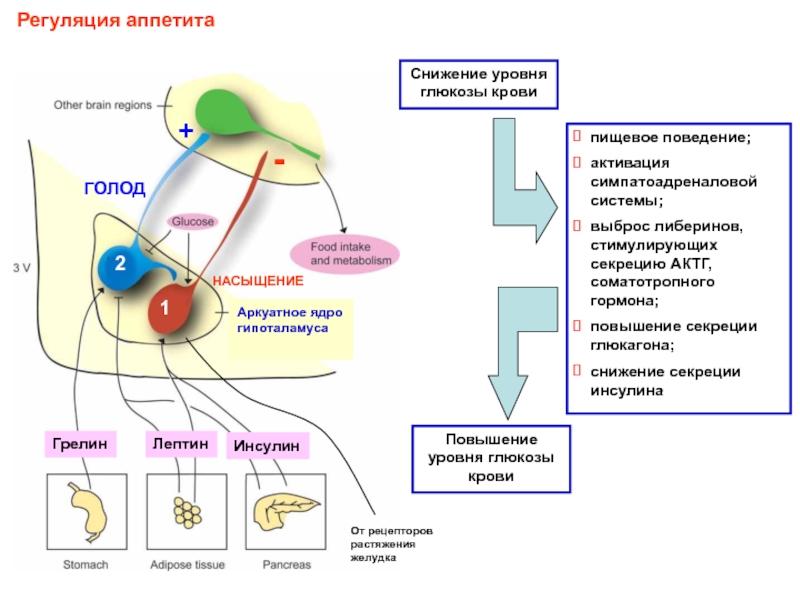

Как работает центр насыщения в гипоталамусе: визуальные иллюстрации